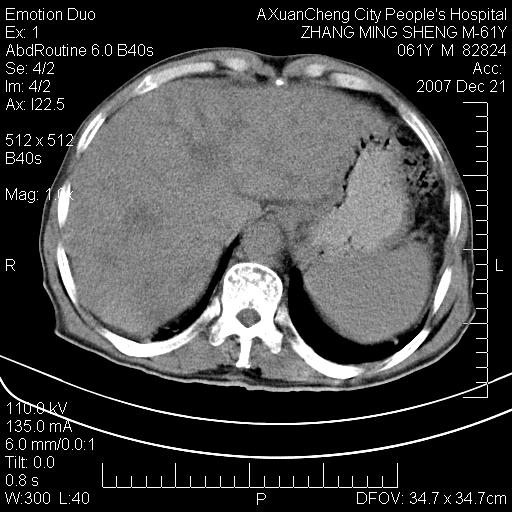

标题: CT11031:M61Y,胰腺占位 [打印本页]

标题: CT11031:M61Y,胰腺占位

大家侃侃门静脉和胆管系统怎么回事,肝内转移?

胰腺癌肝转移

肝硬化,门脉高压,脾肿大;弥漫性肝癌,肝内、门脉、腹膜后淋巴结转移,肝内外胆管扩张,胰头区占位,建议mr检查

胰腺癌伴肝内转移;门脉、肠系膜上v癌栓形成。

考虑为:胰腺癌伴肝脏转移、腹膜后淋巴结转移,门静脉及肠系膜上静脉瘤栓形成。

胰体尾癌伴肝内转移,门静脉及肠系膜上静脉瘤栓形成.

肝硬化,脾大. 胰腺癌伴肝内转移;门脉、肠系膜上v癌栓形成。